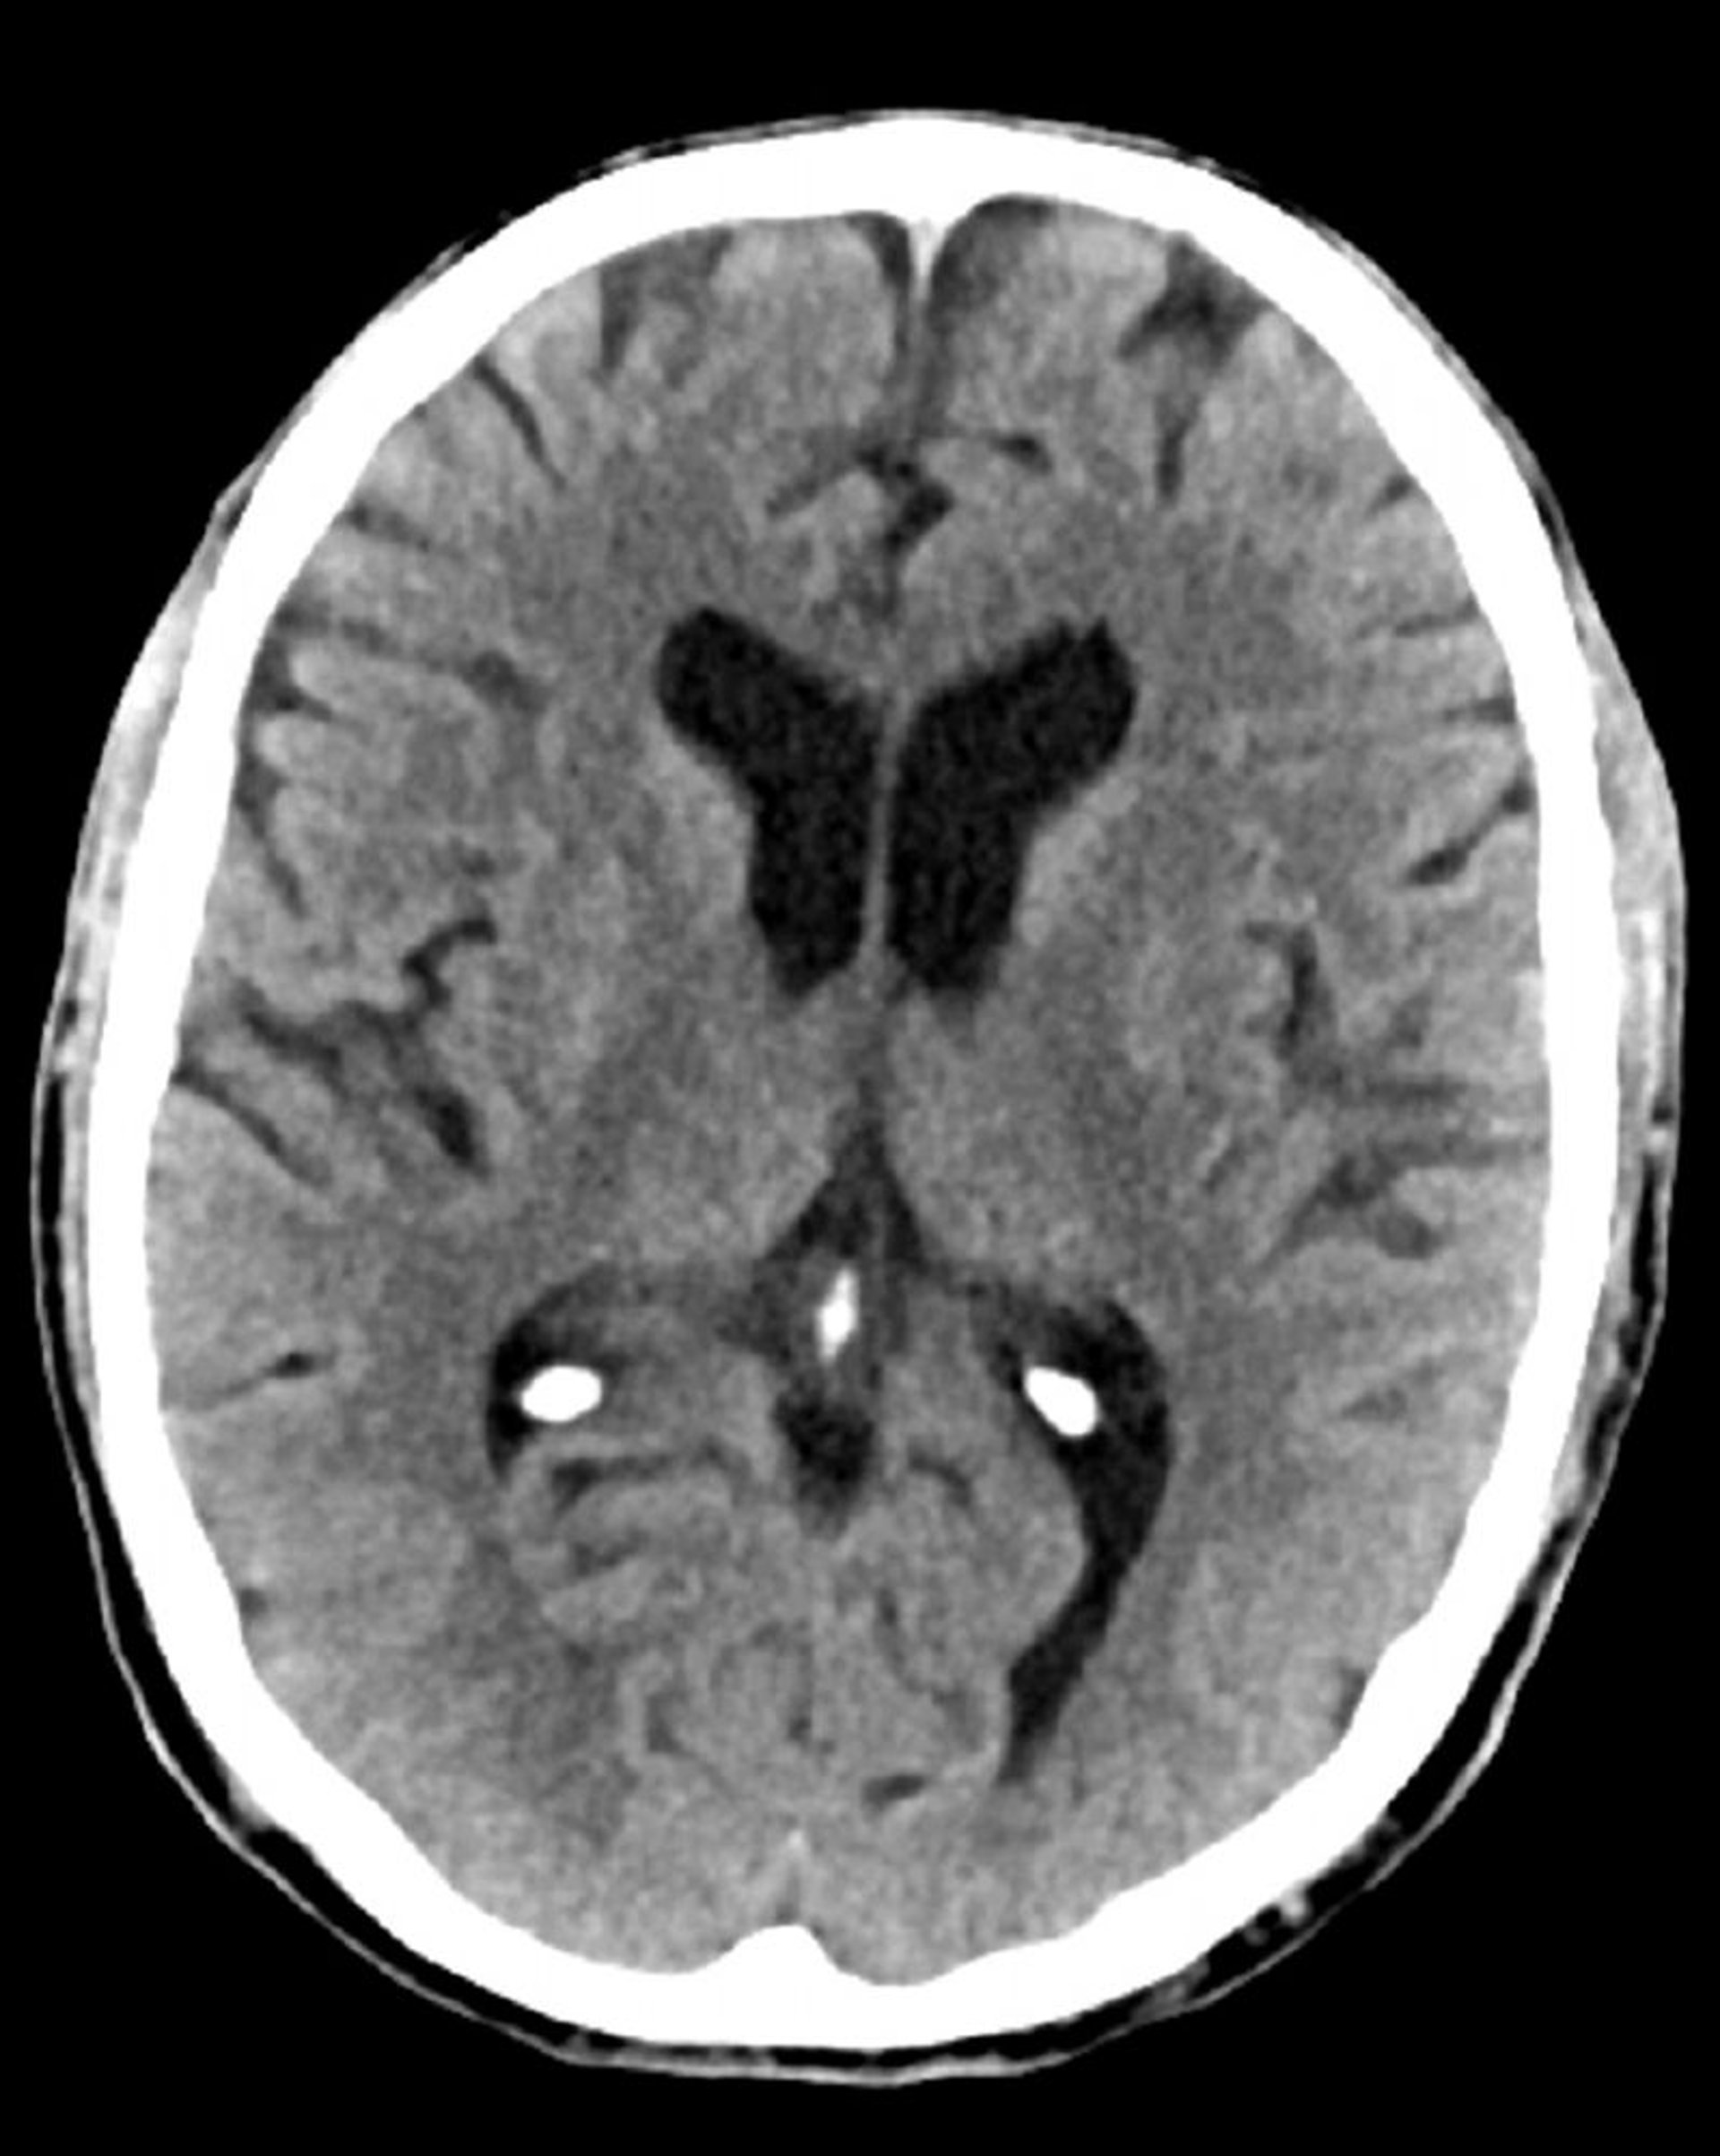

Normal Head CT Scan (Adult, Age 74) – Slide 5

This image is a normal CT scan of the head of an adult aged 74. When compared with the normal CT scan of the head of a 30-year-old, the ventricles and sulci are larger. These findings are normal in this age group.